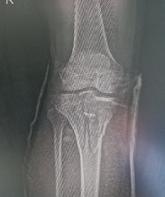

Schatzker III, Osteosinteză cu șuruburi percutană

Schatzker VI, Reducere sângerândă și osteosinteză cu 2 plăci

În fracturile Schatzker I, fără leziuni de menisc extern asociate este indicată reducerea și osteosinteza percutană cu șuruburi. Dacă leziunea de menisc este evidențiată pe RMN, se poate opta pentru reducere și osteosinteză percutană cu șuruburi asociată cu artroscopie(12), având rol de control al reducerii și curativ pentru leziunea de menisc, sau reducere deschisă și fixare internă cu placă și șuruburi.

La pacienții tineri cu fracturi Schatzker tip II și III se poate opta pentru reducere și osteosinteză percutană cu șuruburi asociată cu artroscopie. O altă variantă este cu grefă osoasă și reducere deschisă cu fixare internă cu placă și șuruburi. Controlul reducerii intraoperator se realizează artroscopic sau cu C arm.

Fracturile tip Schatzker IV, fără leziuni asociate, pot fi tratate cu osteosinteză percutană, iar cele cu leziuni ligamentare sau de menisc, cu reducere deschisă și fixare internă.

Fracturile tip Schatzker V și VI sunt rezultatul unor traumatisme cu energie cinetică mare și asociază leziuni tisulare importante. Din această cauză este mai prudent să se temporizeze intervențiile chirurgicale agresive, datorită riscului major de complicații imediate postoperatorii. Fixatorul extern reprezintă o bună alternativă. Are ca și avantaj principal faptul că produce o agresiune tisulară minimă fiind salutar în politraumatisme, leziuni vasculare asociate, fracturi deschise. Dezavantajele constau în dificulta-